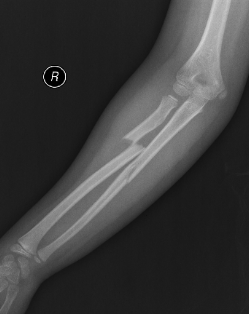

手術前X片:提示患兒尺橈骨干雙骨折,尺橈骨斷端有成角、短縮及移位

手術后X片:提示患兒尺橈骨骨折解剖復位,彈性髓內(nèi)釘置入準確到位